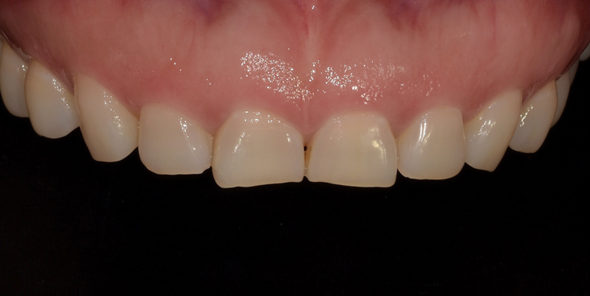

잇몸성형 시술 사례

(전) 2022-09-03 (후) 2022-09-16